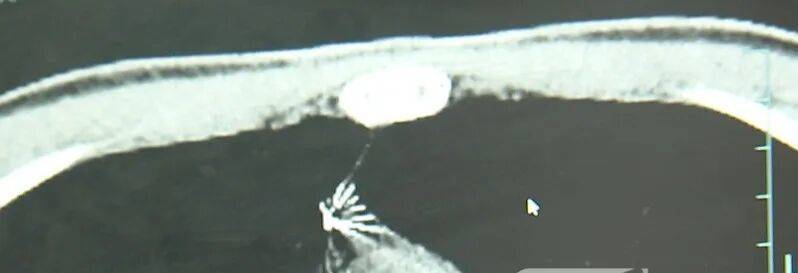

进一步的CT检查确认,异物是一枚金属针,斜插在肺组织内,位置十分凶险。

杭州市第一人民医院心胸外科副主任 冯兴:“我们看到这个针的尖锐部,正好指向他体内的一个大血管,边上是上腔静脉和胸主动脉,因此这个针稍有不慎,就有可能造成周边血管的损伤,甚至危及生命。”

医生推测,那枚针很可能就是在那时候扎入体内的。针在小陆体内滞留了十几年,既没有引发感染,也没有造成气胸,堪称医学奇迹。上周四,医院为小陆实施了mini单孔胸腔镜微创手术,切口仅两厘米左右,成功将针完整取出。